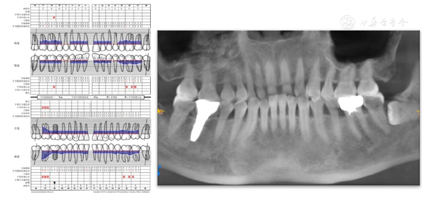

全口牙龈轻度红肿,质地中等,探诊个别位点有出血,PD3~5 mm,BI 1-3,未及松动牙详见牙周检查表(图4)

46种植体冠修复,叩痛(-),不松动,牙龈无明显红肿,PD3 mm,BI1,全口曲面断层片示牙槽骨无明显吸收(图5)。

47叩痛(-),不松动,远中及颊侧中央PD7~9 mm,余位点PD3~4 mm,BI2-3,颊侧中央牙龈退缩约2 mm,无附着龈,舌侧牙龈无明显异常(图6,图7)。正中合未及早接触,侧方合未及合干扰,cbct示47颊侧及远中牙槽骨吸收超过根长2/3,颊侧骨缺损深约9 mm,宽约4 mm,远中骨缺损深约10 mm,宽约7 mm(图8,图9)

36金属全冠修复,叩痛(-),不松动,牙龈无明显红肿,PD3~4 mm,BI1-2,全口曲面断层片示牙槽骨无明显吸收,充填体及髓腔,根管内无阻射影像,根尖周无明显低密度影(图5)。

全口曲断片示(图5):31、32、41、42牙槽骨吸收至根长1/2,余牙牙槽骨普遍吸收至根长1/3,38近中倾斜阻生。